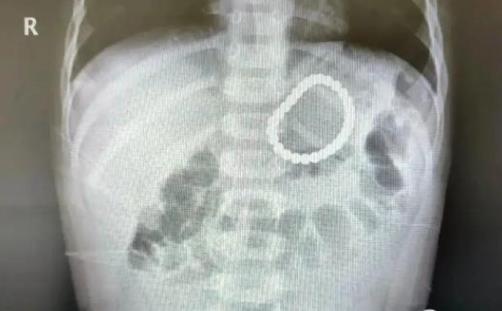

2岁幼童误吞28颗磁力珠 事件经过一出实在让人大吃一惊

导读:2岁幼童误吞28颗磁力珠 事件经过一出实在让人大吃一惊。巴克球又称磁力珠,是一款备受欢迎的“网红”玩具,被很多家长认其有益于“开发大脑”、“拓展思维”和“提升动手能力”。

但对婴幼儿来说,这款玩具却暗藏着一定的危险。